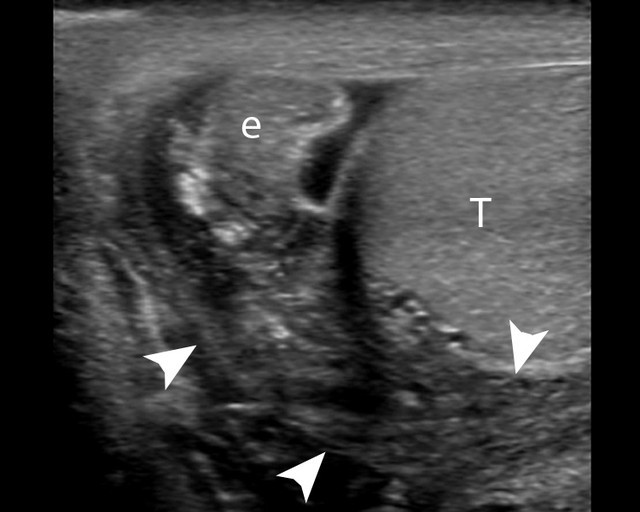

Chẩn đoán bệnh, bác sĩ kiểm tra phản xạ của bệnh nhân bằng cách chà xát hoặc véo mặt trong đùi phía bên tinh hoàn bị xoắn: ở người bình thường, tinh hoàn sẽ co lại, còn ở bệnh nhân bị xoắn tinh hoàn thì phản xạ này không có, tức là không thấy tinh hoàn co lại. Siêu âm Doppler màu: có thể phát hiện bệnh dựa vào lưu lượng máu đến tinh hoàn giảm.

![]() |

Hình ảnh siêu âm xoắn tinh hoàn. |

Scan phóng xạ (Radionuclide scans) có độ chính xác đến 90-100% để phát hiện lưu lượng máu đến tinh hoàn suy giảm. Biến chứng nguy hiểm của xoắn tinh hoàn là: hoại tử tinh hoàn; nhiễm khuẩn tinh hoàn bị xoắn; vô sinh do mất tinh hoàn; biến dạng tinh hoàn.